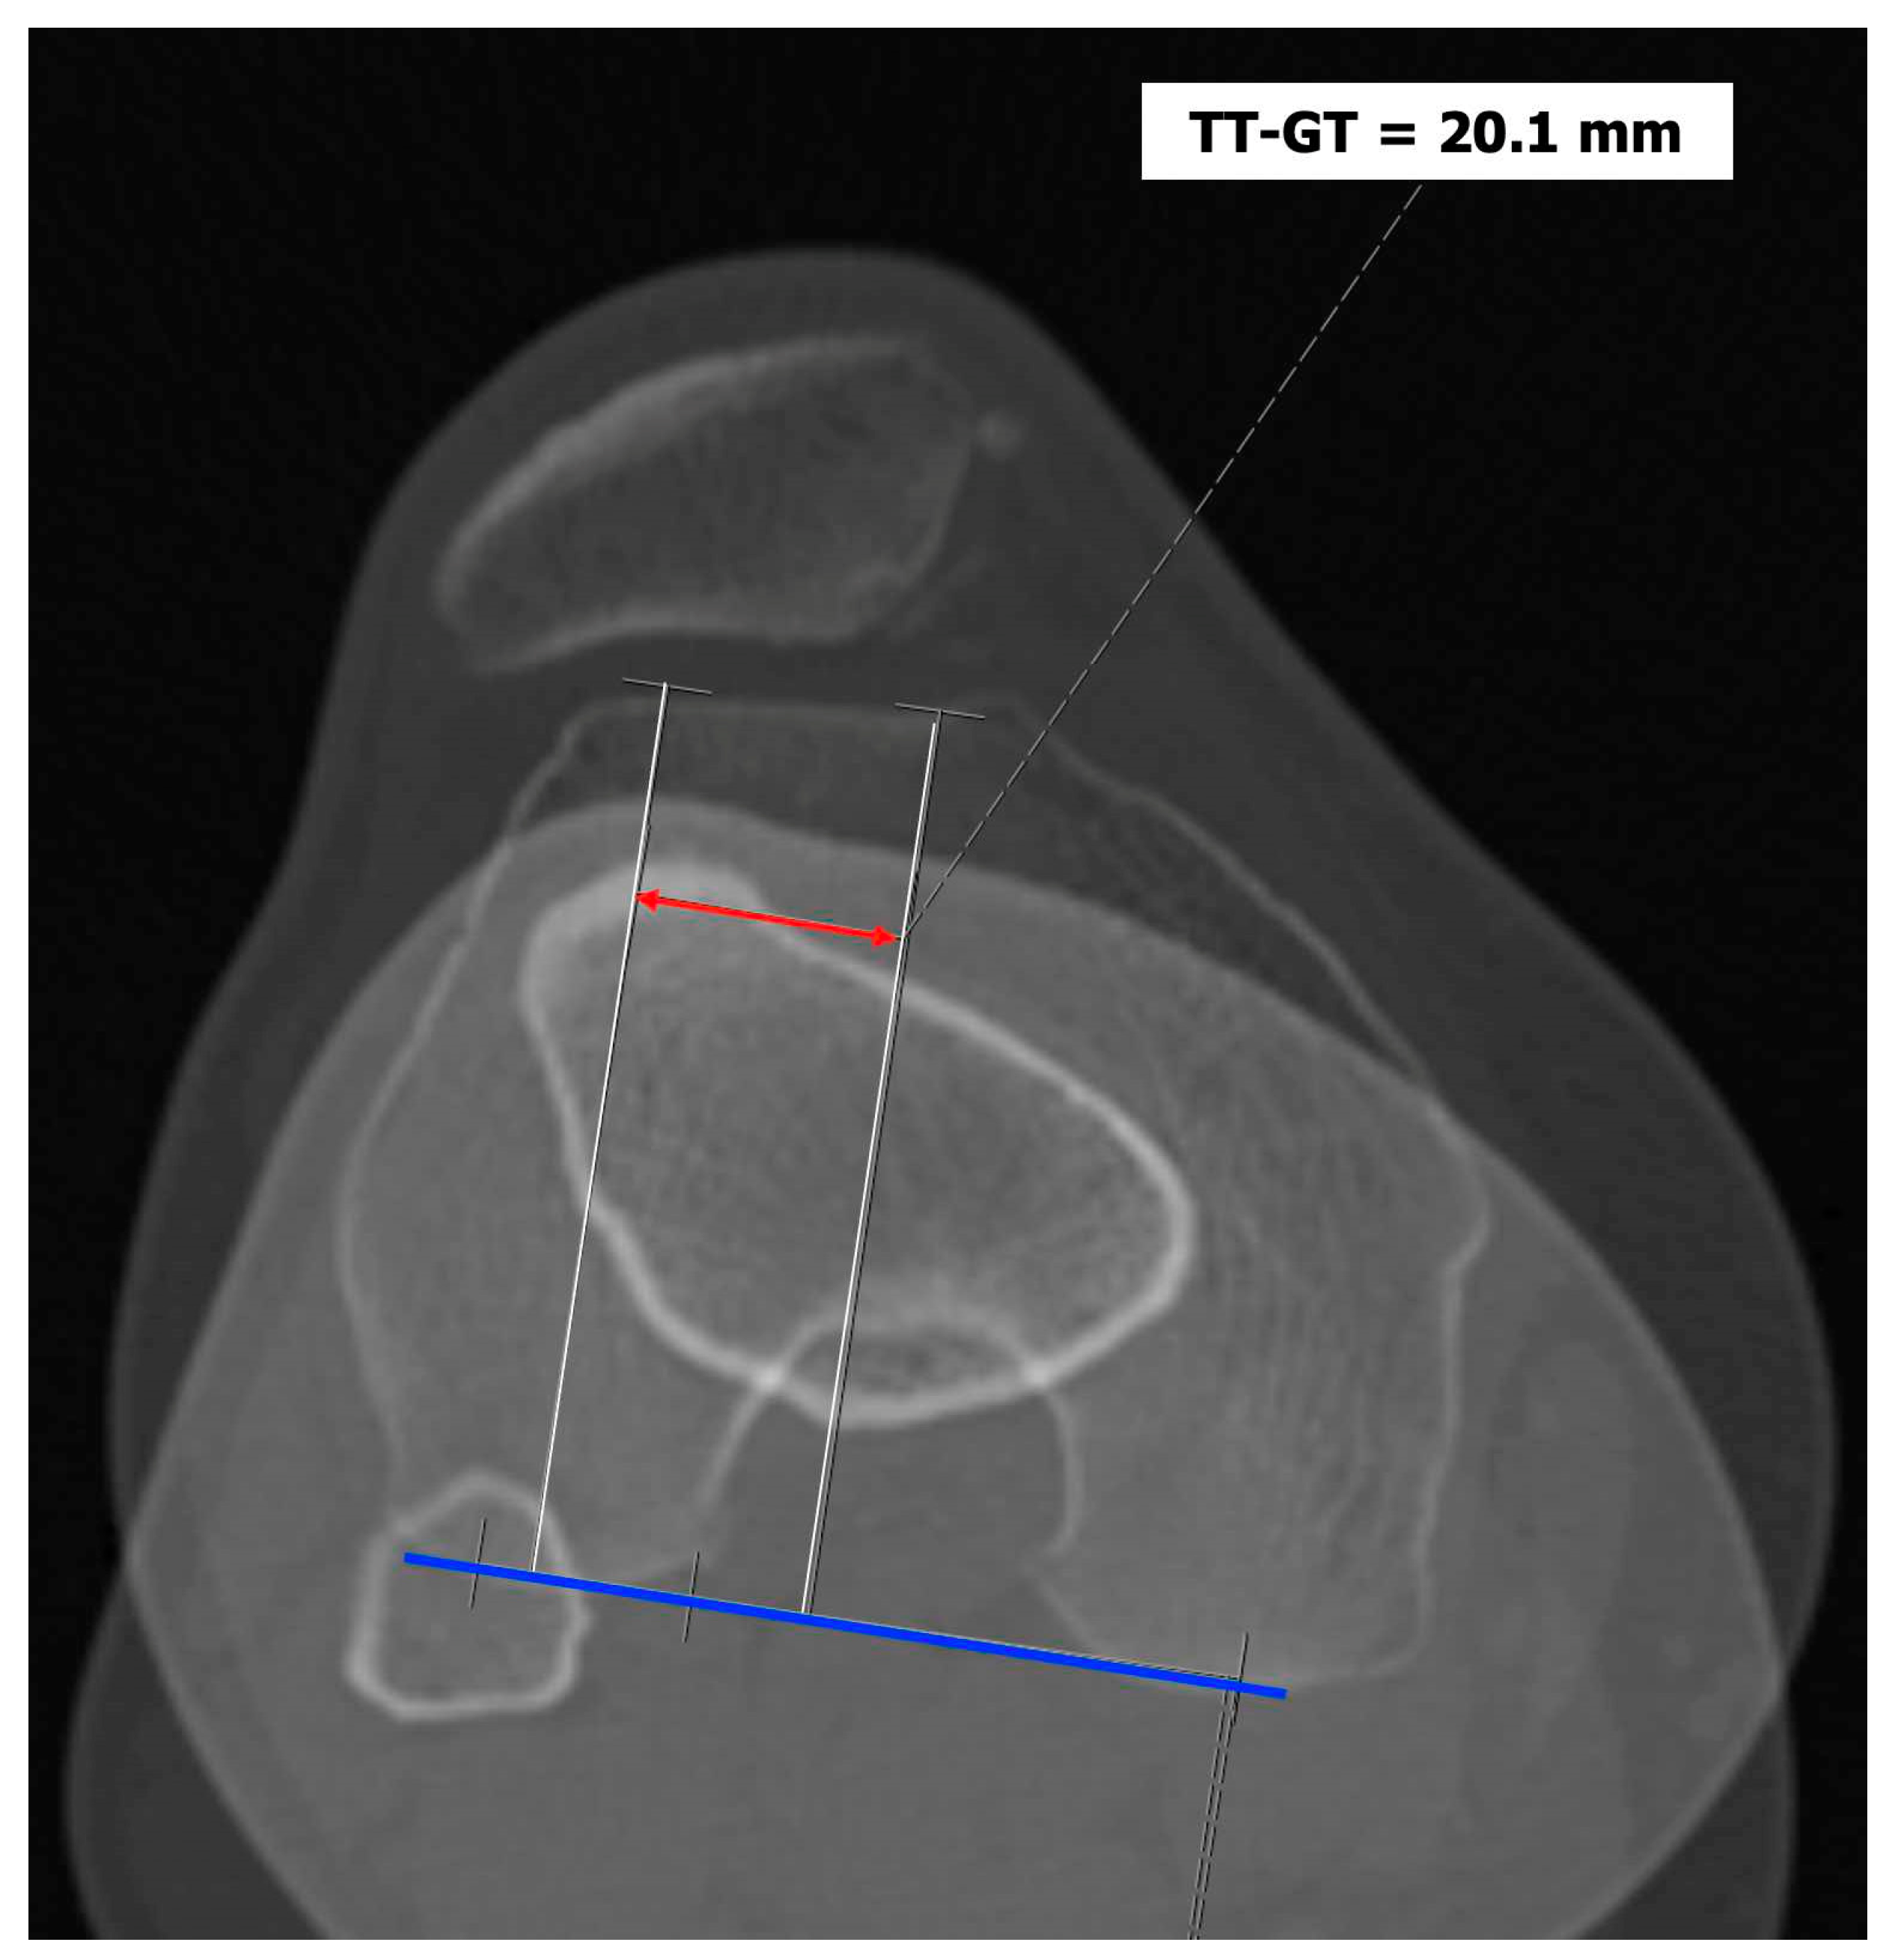

Tibial tuberosity-trochlear groove (TT-TG) distance [12,13]: it is defined as the transverse length between the most prominent point of the tibial tuberosity and the trochlear groove on the femur calculated on axial images (CT scan or MRI), representing axial malalignment of the extensor mechanism. The greater the distance, the greater the lateralizing force acting on the patella. It is pathological when TT-TG > 13mm on MRI or TT-TG > 20mm on CT scan (Figure 4 and Figure 5).

Figure 5. CT scan with pathological TT-TG of 20.1 mm.